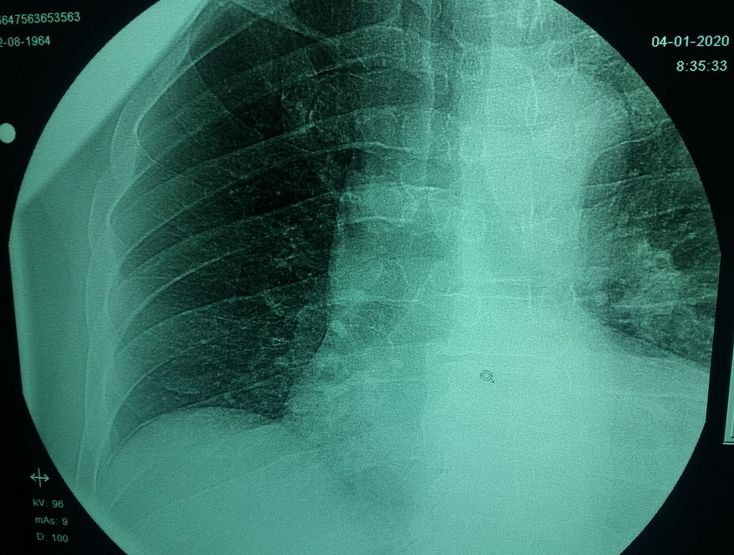

Derrame paranumonico

Boot shaped heart =tetralogy of fallot

Boot shaped heart: characteristics of tetralogy of fallot.